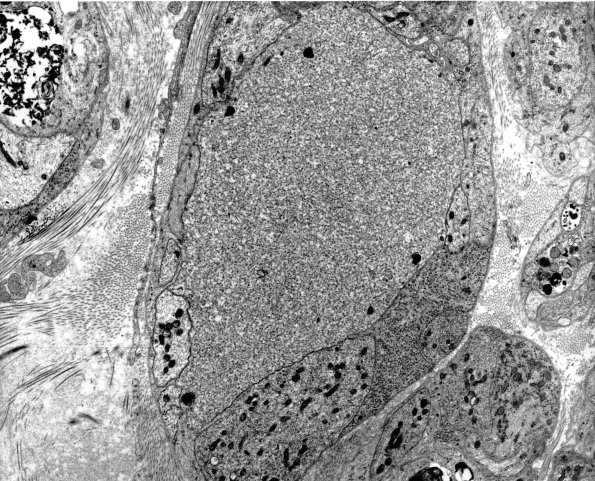

2A6 (IV-55) EM 65

Higher magnification of image 2A5. (electron micrograph)